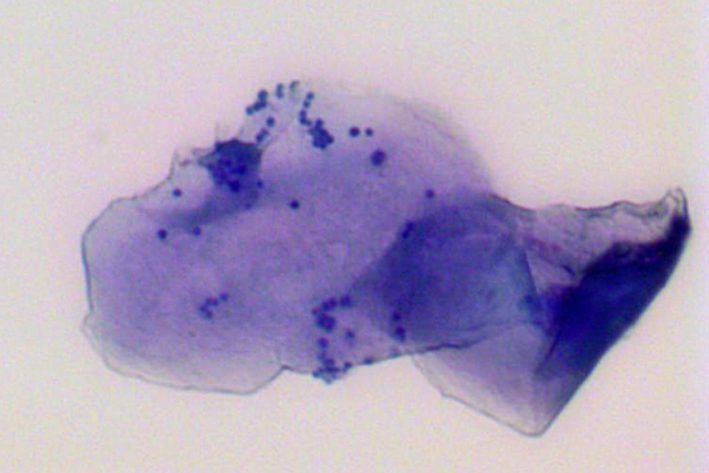

zytologisches Abklatschpräparat: bakterielle Überwucherung

Ein zytologisches Abklatschpräparat unter dem Mikroskop: zahlreiche Bakterien (blaue, gleichförmige Kugeln) heften auf einer Hautzelle: Bakterielle Überwucherung